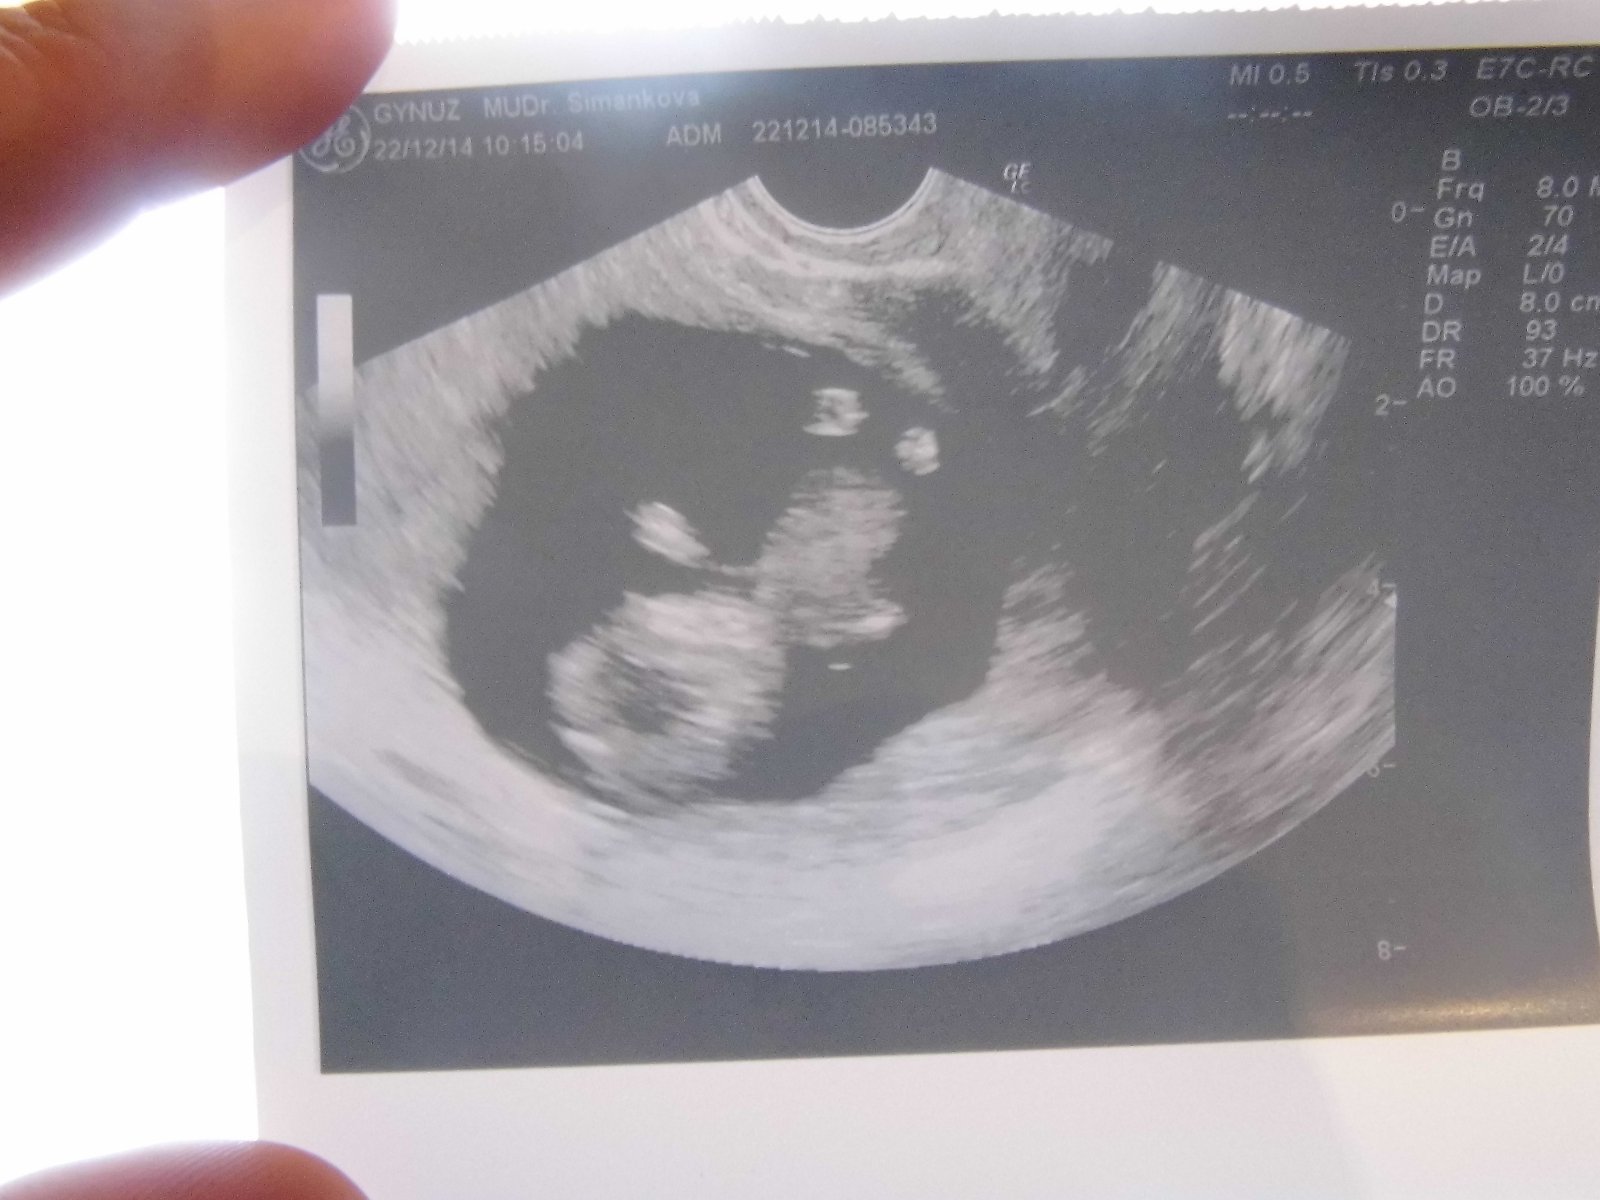

@muddledgirl Ahoj holky, tak takhle rosteme, toto je dnešní UTZ, tj 14tt. A na 90% to bude princezna 😀 Všechno je v pořádku a jsme zdraví!